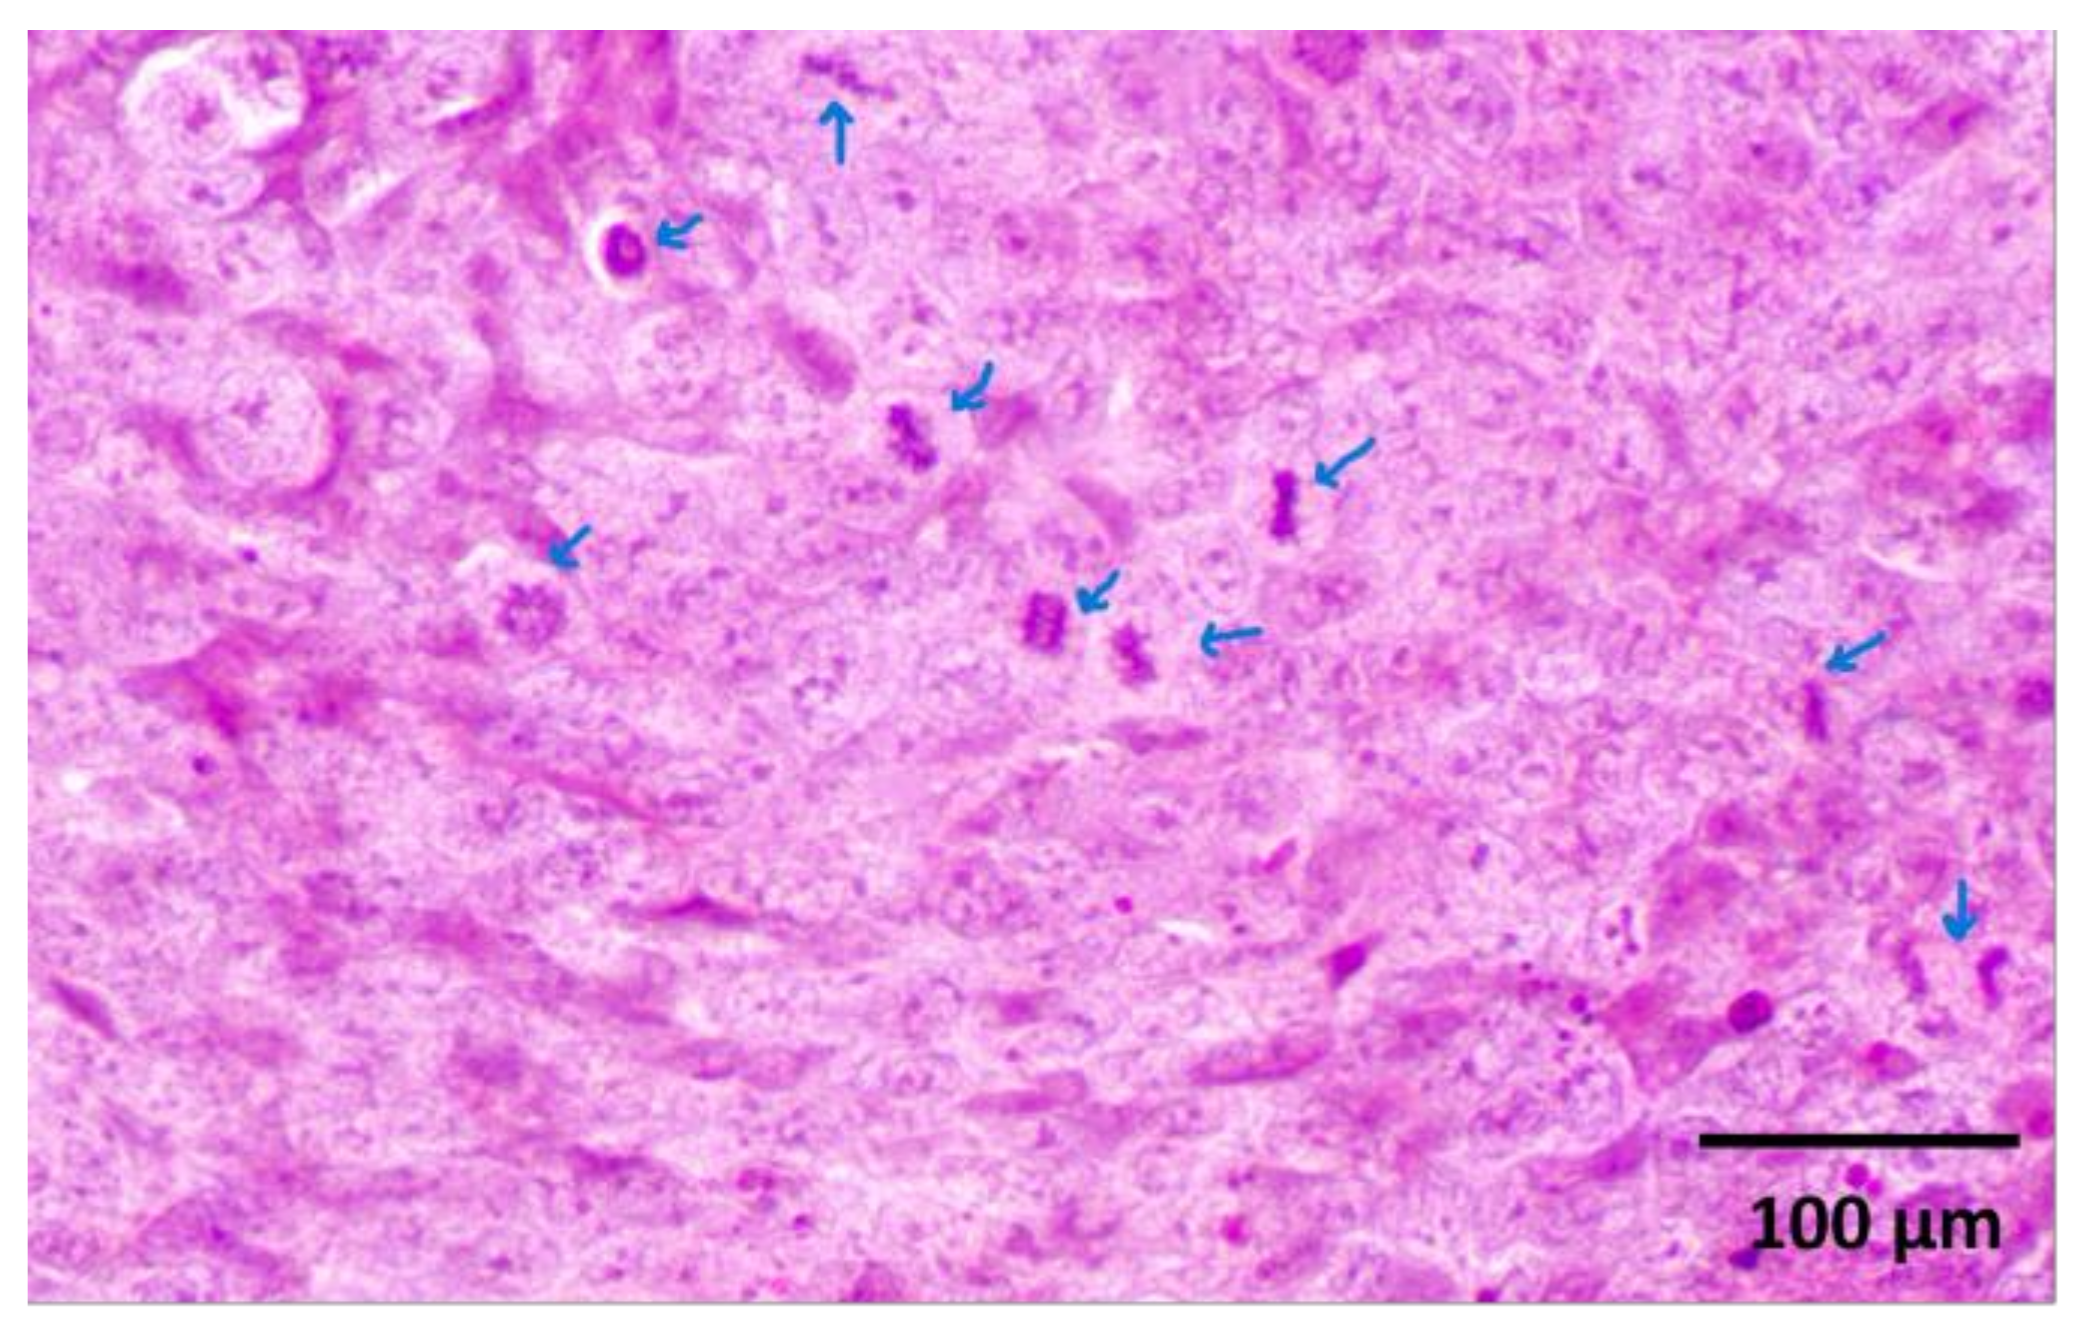

2.1. Histological Evaluation

Histological examination revealed a palpable subcutaneous tumor that was a moderate to low differentiated colon carcinoma, depicted in Figure 1a,b; it thus provided indispensable evidence for their classification in the experimental spectroscopic analysis. Each tumor mass was surrounded by fibrous stroma, as indicated by the black arrow in Figure 1a. The tumor cells were enlarged with round or oval nuclei, and the mitotic activity was increased, as illustrated in Figure 2. The central regions of the tumors were necrotic with hemorrhage, tumor-infiltrating cells, and macrophages, as can be observed in Figure 3a,b. Finally, the Foci of PAS-positive mucin-producing tumor cells are also observed and illustrated in Figure 4.

Figure 3. (a). Tumoral necrosis with hemorrhage and tumor-infiltrating cells (arrows). H&E staining X 100. (b). Intratumoral and peritumoral necrosis and hemorrhage. H&E staining X200.